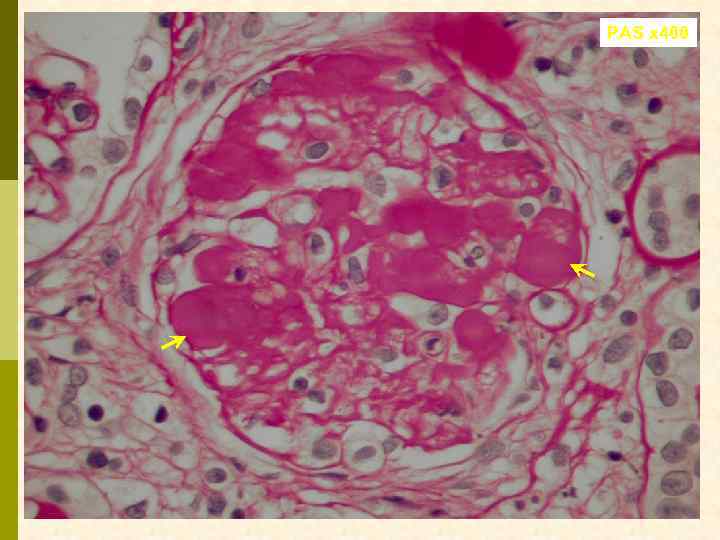

PAS x 400

PAS x 400

Предварительное гистологическое заключение: p Мембрано-пролиферативный, HCV-ассоциированный, криоглобулинемический(? ) гломерулонефрит с полным склерозом 47% клубочков, сегментарным склерозом 22% клубочков и формированием полулуний в 15% клубочков; p диффузно-очаговый выраженный острый канальцевый некроз; p выраженный артерио-артериолосклероз. Примечание: Криоглобулинемическая природа поражения будет уточняться при ЭМ-исследовании.

Заключение p Мембрано-пролиферативный гломерулонефрит, криоглобулинемический, ВИЧ-ассоциированный, на фоне гепатита С